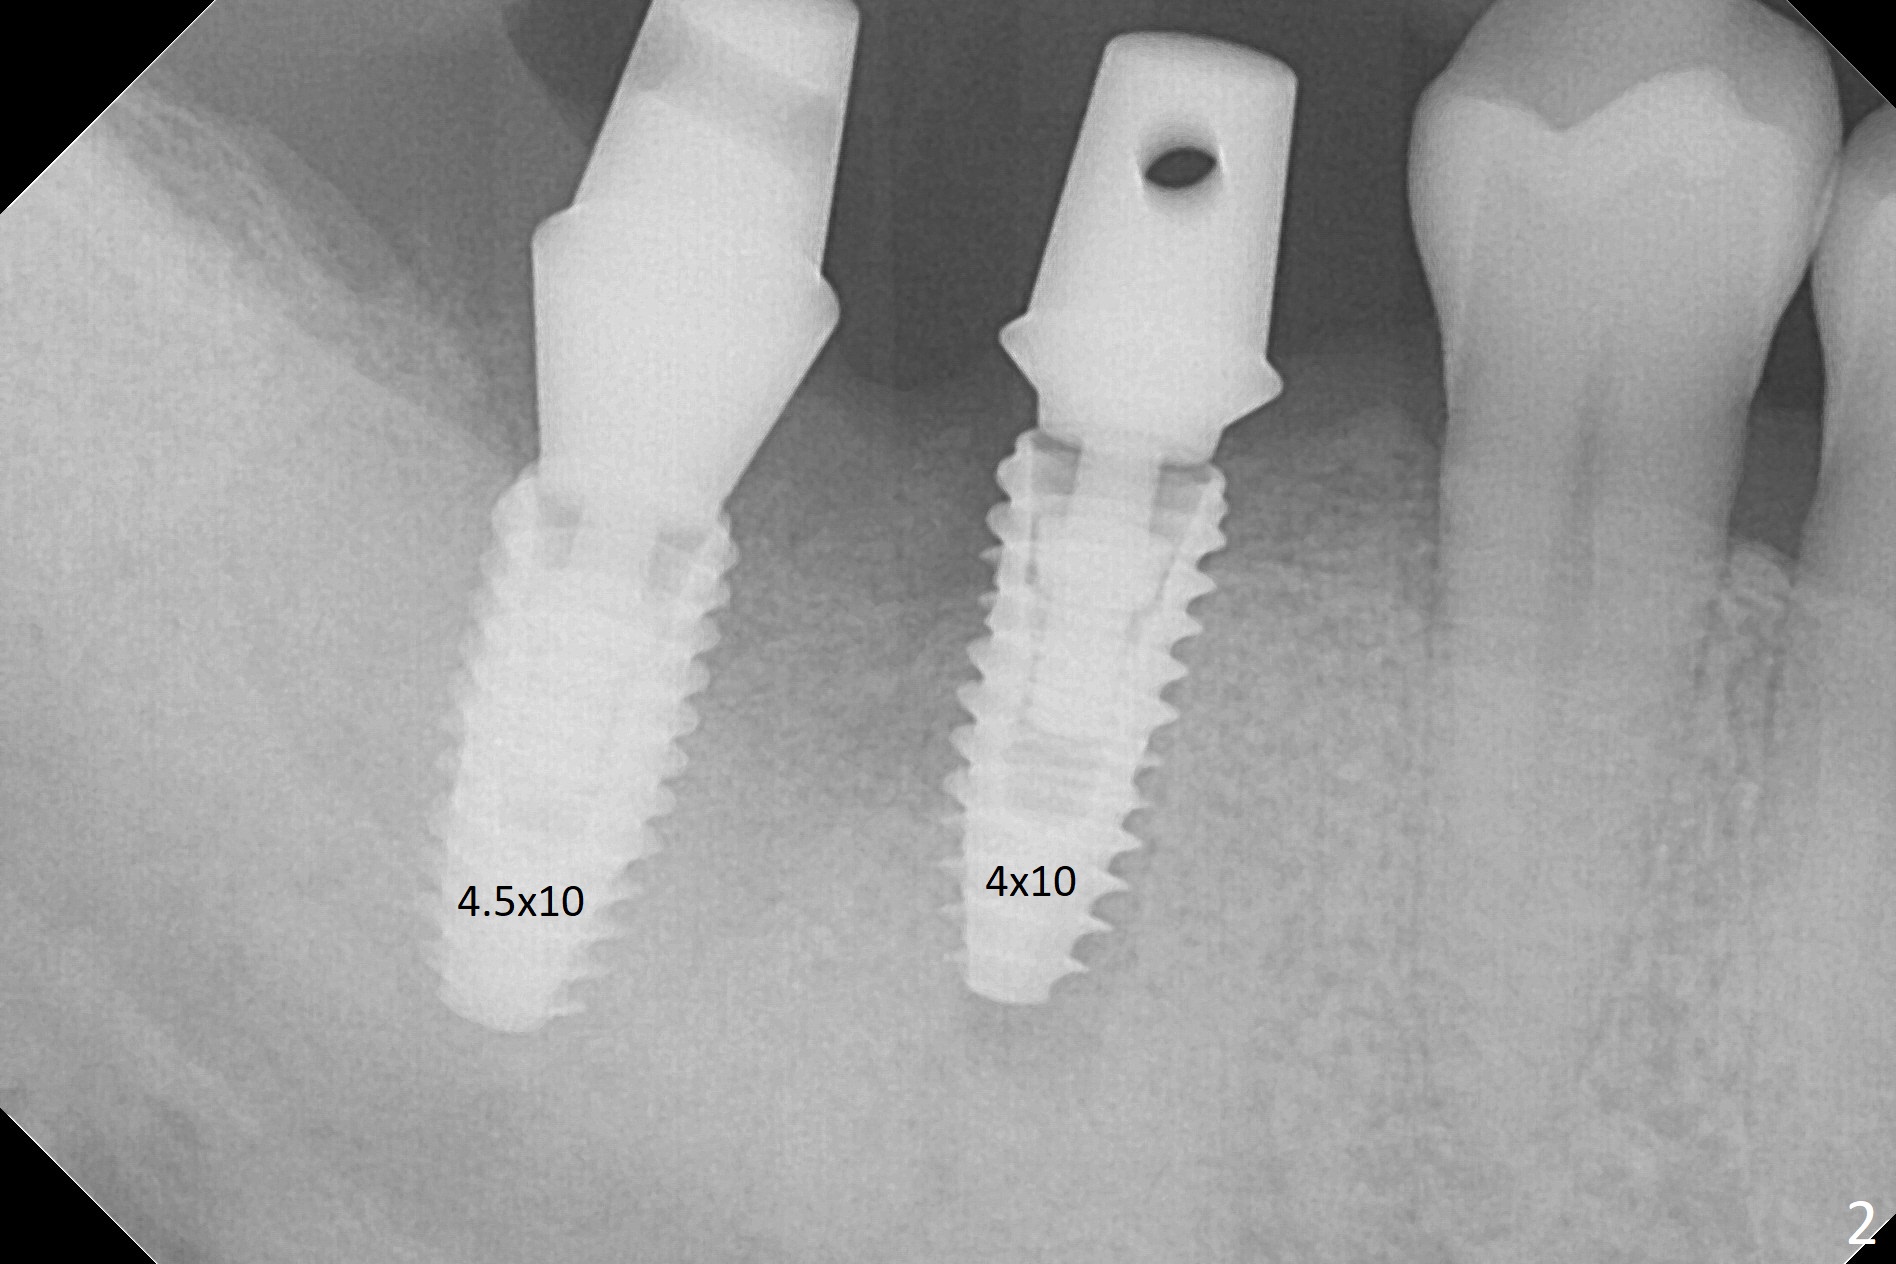

Osteotomy at the sites of #30 and 31 is initiated with Magic Split, followed by Magic Expanders (3.0 and 3.8 mm) at #31.  Initial depth of osteotomy is 13 mm with 2.2 mm drill (Fig.1).  After adjustment of the trajectory at #31 (Fig.1 arrow) and deepening the osteotomy by 2 mm, dummy implants are placed with stability (Fig.2).  Following increase in osteotomy at #31, the larger implant in fact loses stability (Fig.3).  The loose implant is pushed distal (Fig.4 arrow) with placement of autogenous bone mesial (*).  The stable implant at #30 (Fig.3) and its abutment (Fig.4) are used as a post to hold periodontal dressing, which covers the wound at #31 after placement of collagen plug and suturing.  In fact the same technique could be used when socket preservation was performed if an implant were placed at #30 at the same time.  When the periodontal dressing dislodges, the wound at #31 heals uneventfully (Fig.5,6).  The bone graft seems to remain in place 3 months postop (Fig.7).  The implant is uncovered with placement of a 6.8x7 mm healing abutment 4 months postop.  When a cementation abutment is placed and prepped, the buccal margin is much lower than the lingual (Fig.8 taken prior to cementation).  The patient enjoys mastication with the new implant crowns 3.5 months post cementation (Fig.9).